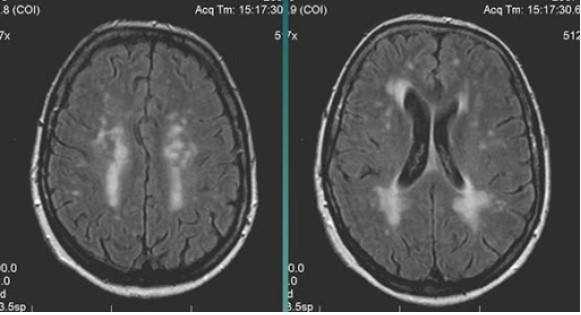

МР-снимок показывает дистрофические изменения белого вещества вокруг желудочков мозга, характерные для хронической ишемии (лейкоареоз)

Хроническая ишемия головного мозга - прогрессирующее состояние, имеющее стадийность развития. Причиной с высокой долей вероятности могут быть атеросклеротические изменения артерий, гипертония и колебания глюкозы крови.

- лейкоареоз — изменение белого вещества вокруг желудочков головного мозга (на рисунке 1, белое свечение вокруг желудочков);

- лекоэнцефалопатия — поражение белого вещества головного мозга (на рисунке 1 и 3, светлые участки в подкорковом веществе);

- малые инфаркты, ишемические инсульты (рисунок 3);